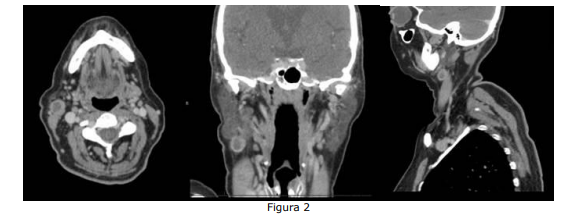

Paciente com diagnóstico de CEC de língua metastático para linfonodo cervical realizou TC de face e pescoço, mostrada na Figura 2 abaixo:

Com base na Figura 2, assinale a alternativa que indica o nível cervical em que se encontra a metástase em questão.